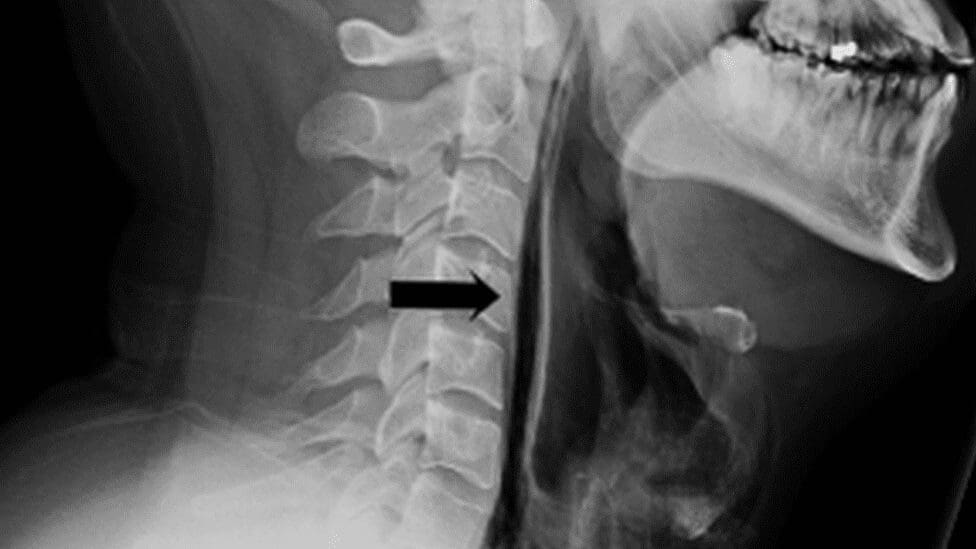

Normalmente, el estornudo permite expulsar aire a gran velocidad para liberar partículas e irritantes de las vías respiratorias. Cuando se evita que esta expulsión ocurra, la presión que debería salir por la nariz y la boca se redirige de manera interna. Como consecuencia, pueden ocurrir diversas afectaciones, entre ellas la ruptura de pequeños vasos sanguíneos en los ojos, daños en el oído interno o malestar en la garganta debido al impacto del aire comprimido.

En casos más serios, esta presión contenida puede llegar a comprometer estructuras más delicadas del sistema circulatorio y respiratorio, lo que podría provocar problemas de respiración o incluso elevar el riesgo de aneurisma cerebral. Un aneurisma se produce cuando una arteria presenta una dilatación anormal y debilitada, que puede agravarse con aumentos bruscos de presión.